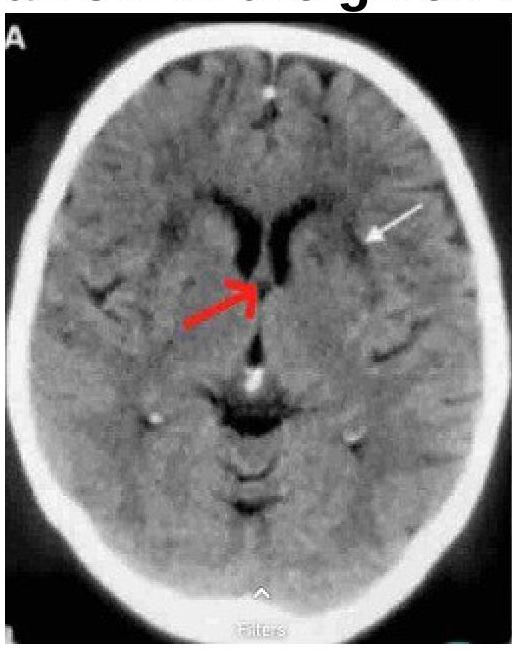

Identify the structure marked by a red arrow in the image.

Explanation: ***Fornix*** - The **fornix** is a C-shaped bundle of nerve fibers in the brain that acts as the primary efferent (output) pathway from the hippocampus. - On an axial CT image, the fornix is typically seen as a **thin, arching structure** located above the third ventricle and below the corpus callosum, which matches the position indicated by the red arrow. *Great vein of Galen* - The **Great cerebral vein of Galen** is a large midline vein located posterior to the third ventricle and pineal gland, draining into the straight sinus. - Its position is more posterior and inferior to the structure indicated by the red arrow. *Pineal gland* - The **pineal gland** is a small, endocrine gland located in the epithalamus, posterior to the third ventricle and often calcified, appearing bright on CT scans. - While it's in the general vicinity, the red arrow points anterior and superior to where the pineal gland would typically be visualized. *Falx cerebri* - The **falx cerebri** is a large, crescent-shaped fold of dura mater that dips into the longitudinal fissure between the cerebral hemispheres. - It would appear as a linear structure in the sagittal plane or as a midline divider in some axial cuts, distinct from the deep brain structure indicated by the arrow.